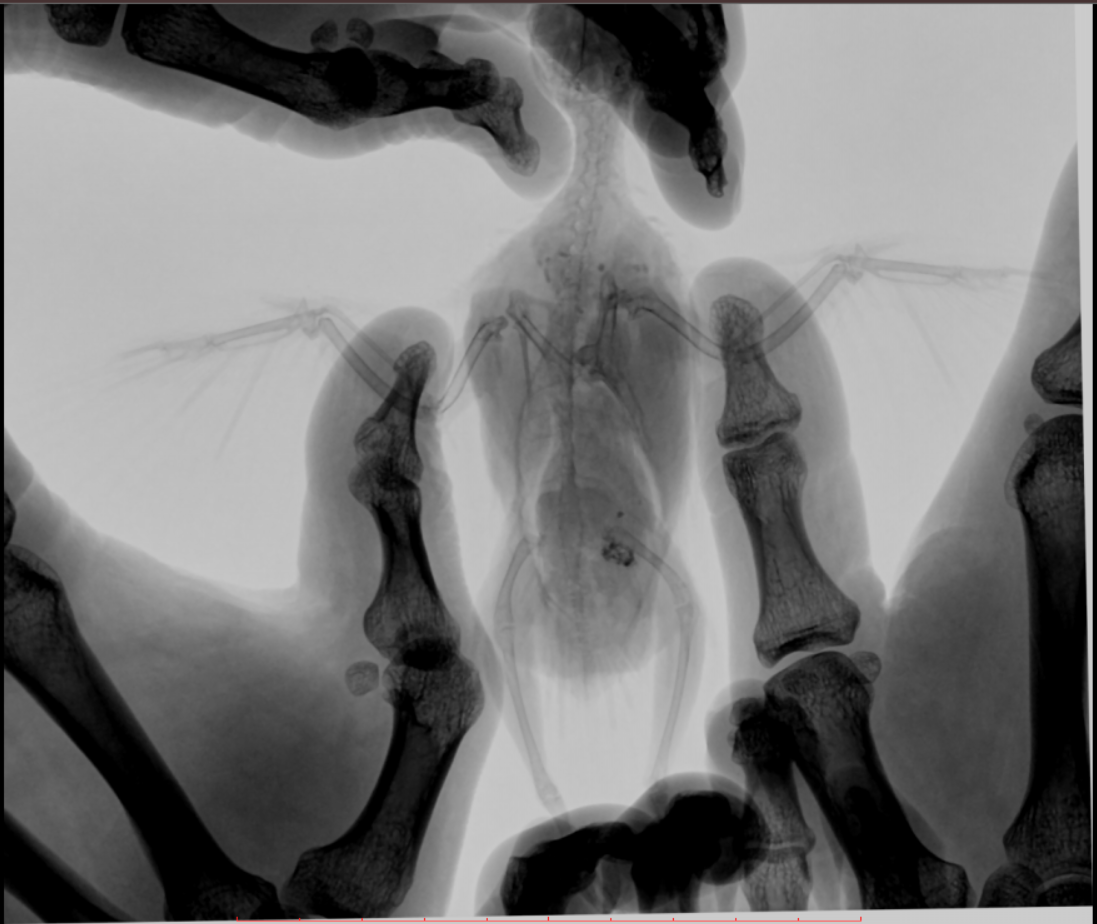

Во вторник отвозила птицу на рентген. Врач сказала, что очень сильно увеличена печень и другие органы. Также сдавлены воздухоносные мешки (из-за увеличенных внутренних органов). Отсюда - одышка. Также врач нашла перелом (старый?) ключицы. Попугая было очень сложно удерживать, поэтому снимки получились, возможно, недостаточно информативными - но какие уж получились((

@Zosia здравствуйте! Посмотрите, пожалуйста, снимки - видите ли вы на них отклонения, опухоли? Есть ли какие-то патологии? И одобряете ли вы назначенное лечение в нашей ситуации? Спасибо!

2.jpg

4.jpg

Печень видится мне увеличенной, но нужно чтобы @Zosia достоверно прочла снимки.

6.Тень семенников действительноу величена. Но снимок вами показан дурного качества. И бОльшего я сказать не могу.